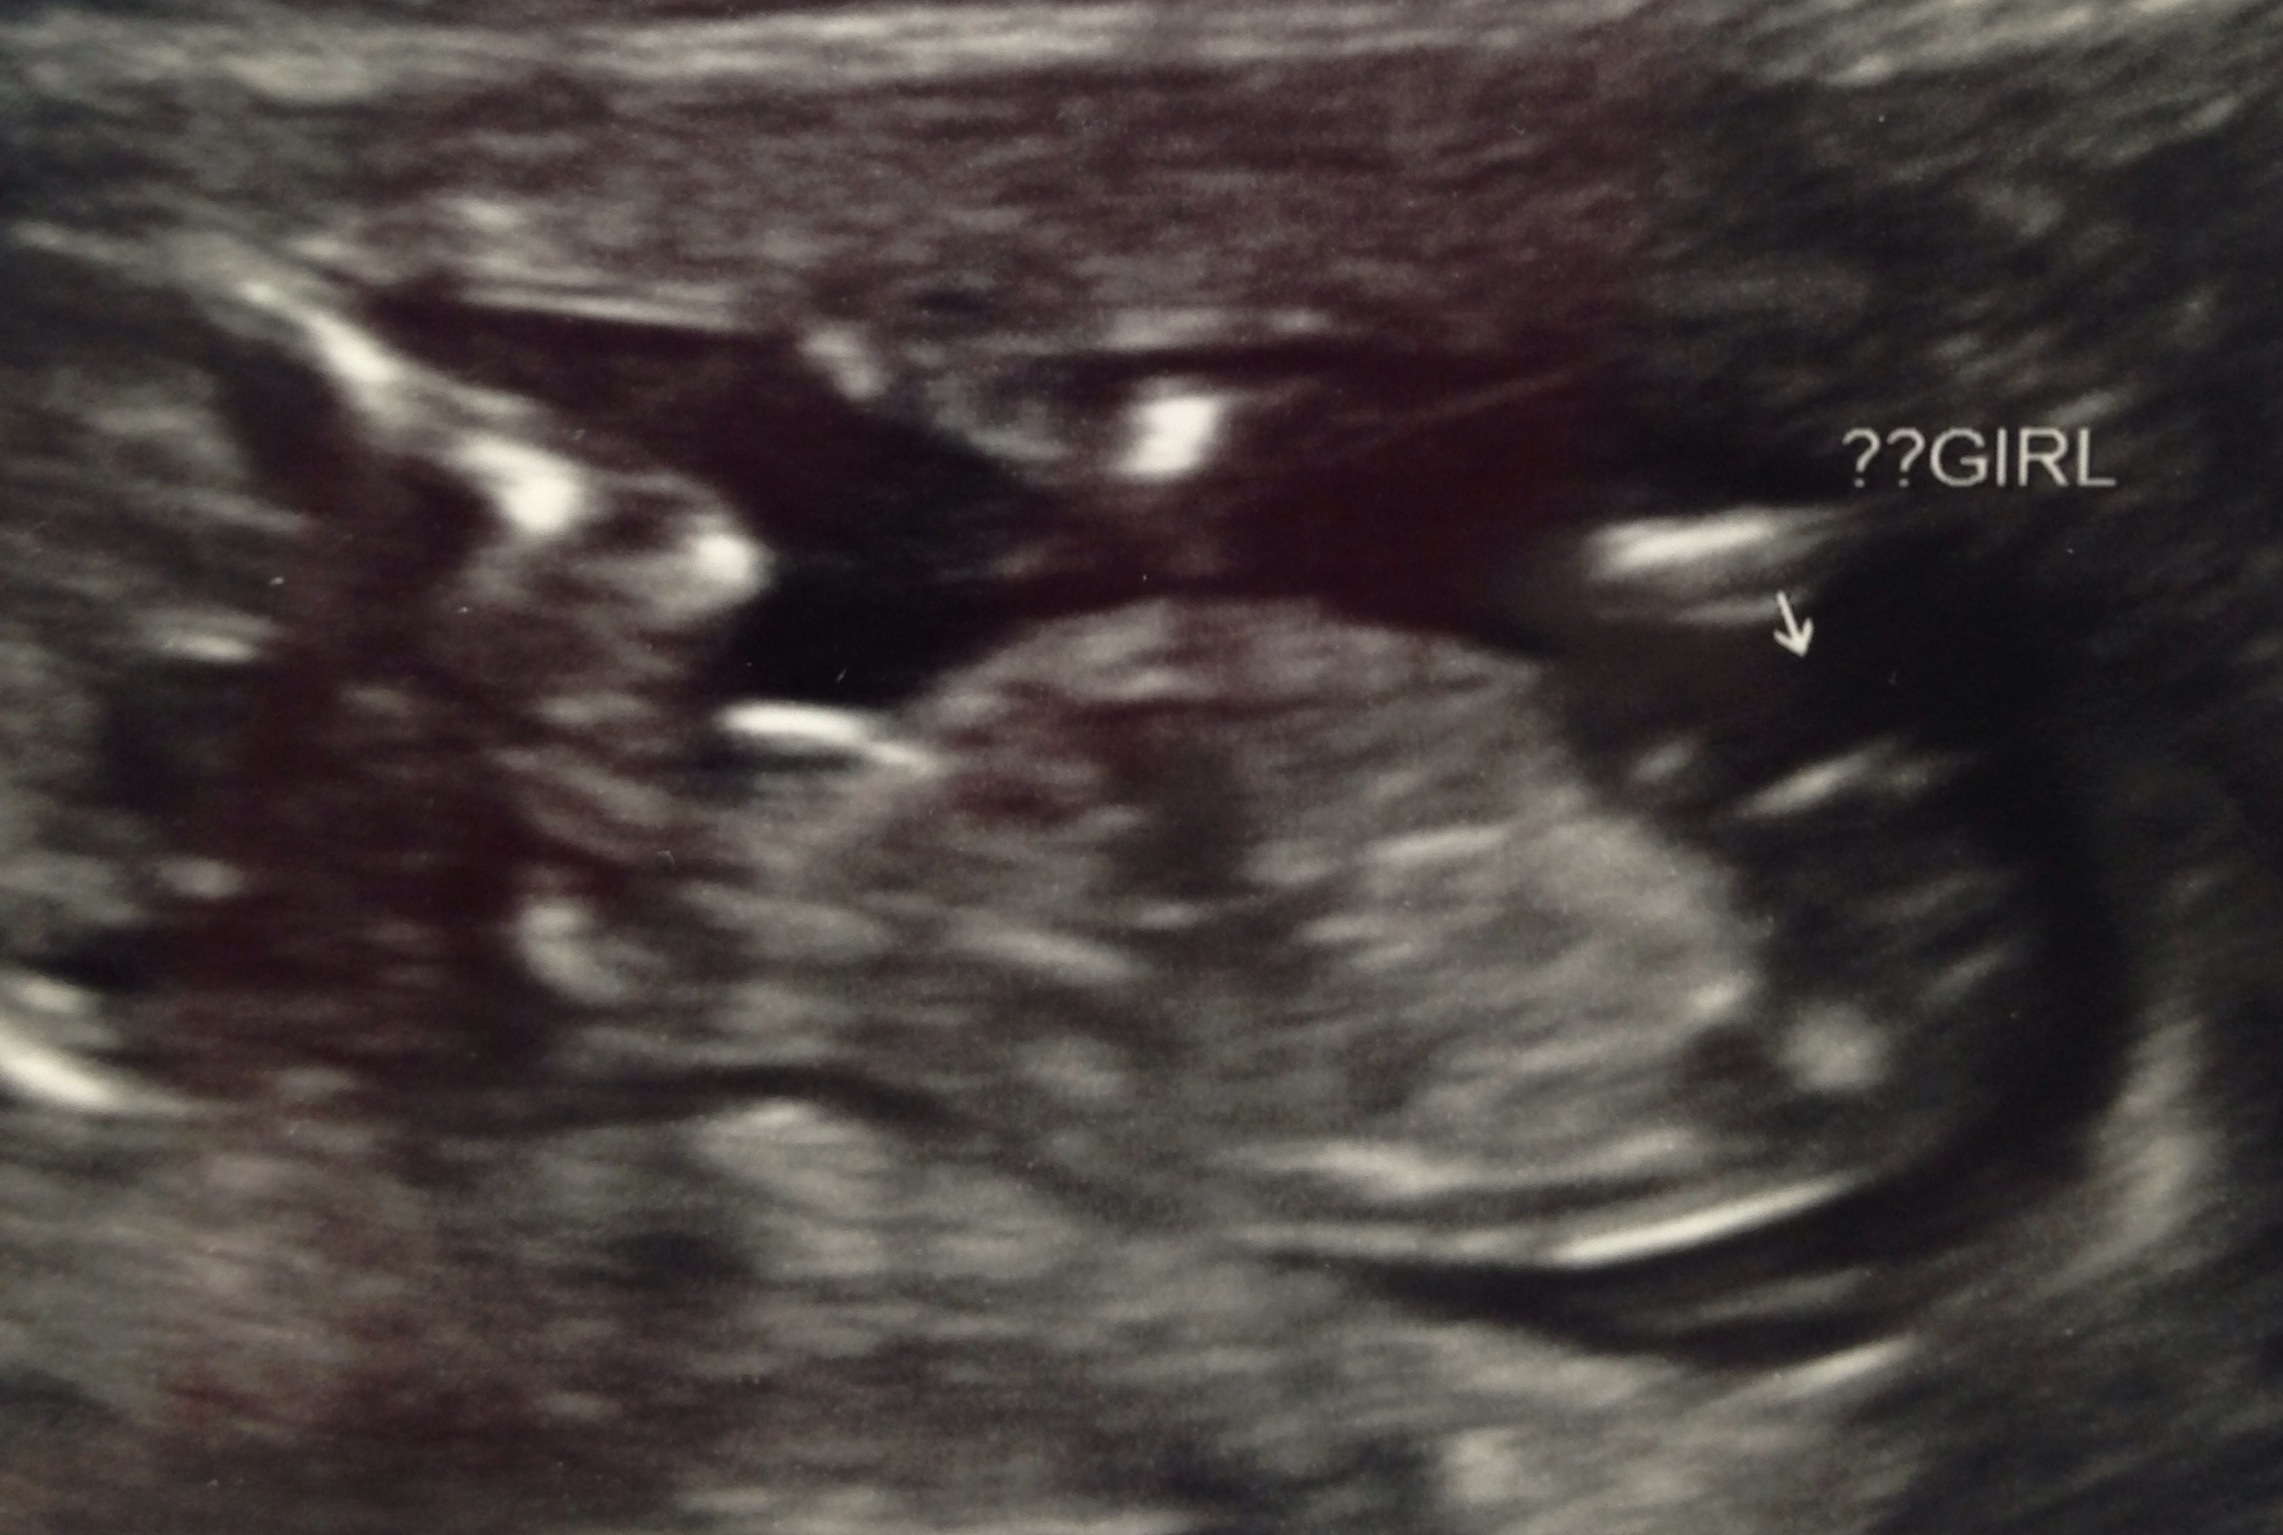

Attachment 17500We had our nt scan yesterday, going by LMP I am 12 weeks 1 day, but baby was measuring ahead at 13weeks 2 days. I got a nub and a potty shot. The tech says she's 80% sure it's a girl. Thoughts and second opinions would be amazing. Thank you very much :) Attachment 17499